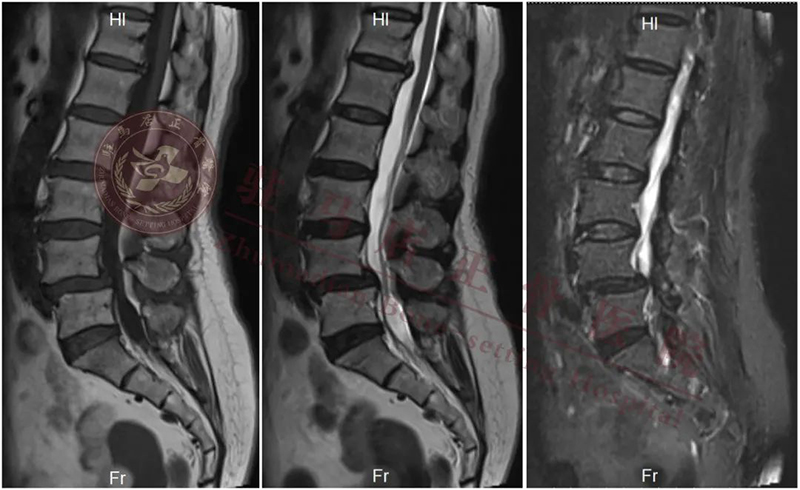

【患者情况】:女性、68岁,职业:农民

【主 诉】:腰痛12年加重伴双下肢疼痛、麻木1年

【诊 断】:1.腰椎管狭窄症(L4/L5); 2.腰椎间盘突出症(L4/L5); 3.腰4椎体滑脱(II度)

【术前计划】:通过影像等相关检查,明确诊断,根据诊断确定手术方式:经内镜下行腰4/5椎间盘切除、椎管扩大减压、椎间植骨融合复位、经皮椎弓根螺钉单侧内固定术

【拟行手术名称】:UBE镜下腰4/5减压融合固定术

{ 术前 }